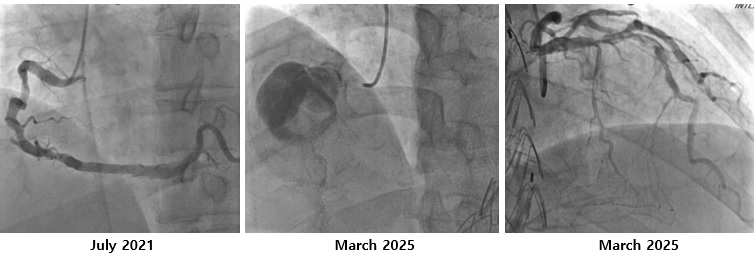

The coronary angiography showed a giant right coronary artery (RCA) aneurysm with total occlusion at mid-RCA and collateral flow from the left circumflex artery. It is different with right coronary angiography at 4 years ago that showed no coronary aneurysm. The left coronary artery has a good flow to the distal without any significant stenosis and patent stent on 1st diagonal artery branch.